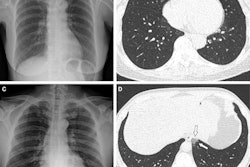

Images in a 64-year-old woman who presented with confusion and collapse and was diagnosed with intracranial hemorrhage associated with cerebral venous sinus thrombosis secondary to VITT. (A) Axial unenhanced head CT image demonstrates a large right parietal lobe intraparenchymal hemorrhage and (B) bilateral infarcts in the cerebellum confirmed on axial brain T2-weighted MRI. (D) CT pulmonary angiogram coronal reformatted image shows eccentric mural thrombus within the aorta (white arrow) and large central saddle embolus (red asterisks). Images and caption courtesy of the RSNA.Experts recommend symptom-specific imaging for VITT, but its prevalence remains unclear, Rogers and colleagues noted. To clarify the question, the group conducted a study that included 40 patients who developed thrombocytopenia after receiving their first dose of the AstraZeneca vaccine. The patients were imaged with CT, ultrasound, and/or MRI depending on protocol in seven different centers across the U.K.

Of these 40 patients, 80% developed thrombosis symptoms within 14 days and 20% within 14 to 28 days. The investigators also found the following:

- 75% of patients underwent additional imaging, primarily with CT pulmonary angiogram or CT of the abdomen or pelvis.

- 83% of those patients who had additional imaging were found to have hidden blood clots.

- 73% of the patient cohort presented with neurological symptoms (headache, blurred vision, seizure, collapse) and were confirmed by CT or MR venogram to have a cerebral venous sinus blood clot.

- 30% had extension of their primary blood clot.

- 20% of the total cohort died (eight of 40); those with confirmed progressive thrombosis (four patients) had a mortality rate of 50%.

Most patients underwent some form of CT imaging, the authors noted.